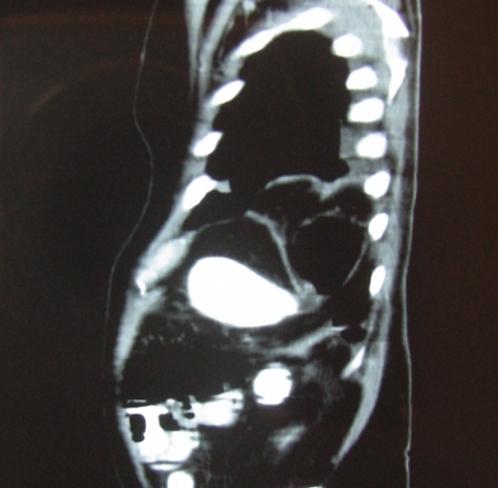

Laparoscopic repair of an incarcerated bochdalek hernia in an elderly man.

Clinics (Sao Paulo). 2012;67(2):199-201. doi: 10.6061/clinics/2012(02)20.